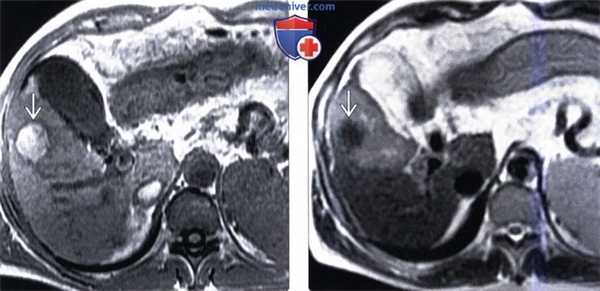

(Слева) На аксиальной Т1 ВИ МР томограмме у пациента с известным гепатоцеллюлярным раком, которому была выполнена артериальная химиоэмболизация, определяется гиперинтенсивное образование, непохожее на жизнеспособную опухоль.

(Справа) На аксиальной Т2 ВИ МР томограмме у этого же пациента определяется нежизнеспособный узел ГЦР, характеризующийся пониженной интенсивностью сигнала, что не характерно для жизнеспособной опухоли.